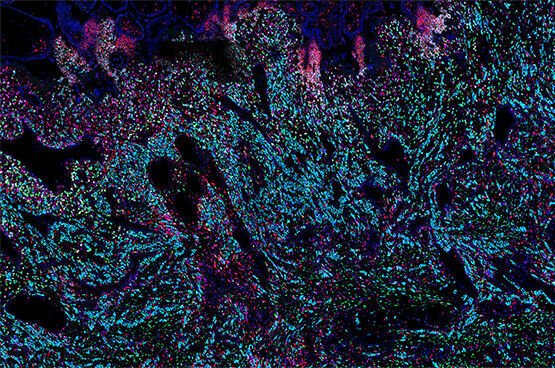

Researchers have revealed what happens in the early stages of placental development, a process crucial for a successful pregnancy. Credits: Kenny Roberts, Wellcome Sanger Institute.

Researchers have revealed what happens in the early stages of placental development, a process crucial for a successful pregnancy. Credits: Kenny Roberts, Wellcome Sanger Institute. For the first time, researchers have mapped the full trajectory of placental development. Their work could offer new insights into pregnancy disorders and help develop better experimental models of the human placenta. Researchers from the FMI led by Margherita Yayoi Turco, the Wellcome Sanger Institute, the University of Cambridge and EMBL's European Bioinformatics Institute have created an in-depth picture of how the placenta develops and communicates with the uterus. The team used single-cell genomics and spatial transcriptomics technologies to analyze a rare historical set of samples, capturing the process of placental development in unprecedented detail. These techniques allowed the researchers to see all the cell types involved in the early stages of placenta formation and uncover how some placenta cells communicate with the uterine environment around them.